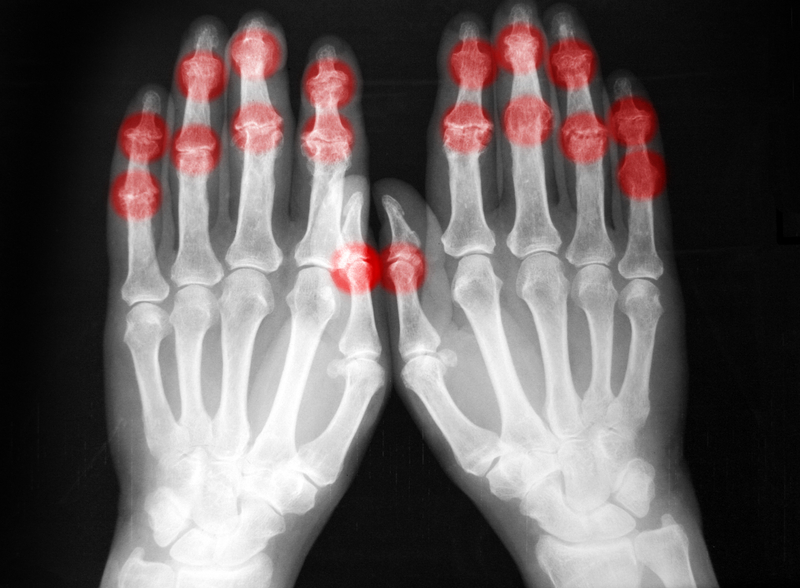

The growing demand for medical imaging procedures has caused an automatic spike in diagnostic investigations, rising complication trends and a nationwide manpower shortage, a radiography expert has said.

Highlighting major challenges in the sector, he listed the “rising demand for imaging procedures, increased volume of investigations, growing complexity of cases and a severe shortage of trained professionals.”

He cited available records showing that Nigeria had 183 CT machines in 2018, with Lagos State having 33, Rivers 13, Oyo 11, Anambra 10, Ogun 8 and Kano 8; while the country had only 58 MRI machines as of 2016.